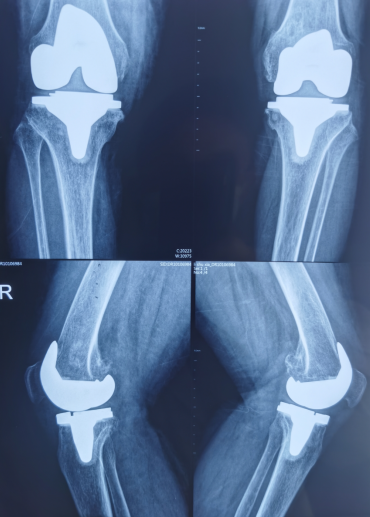

术后膝关节复查